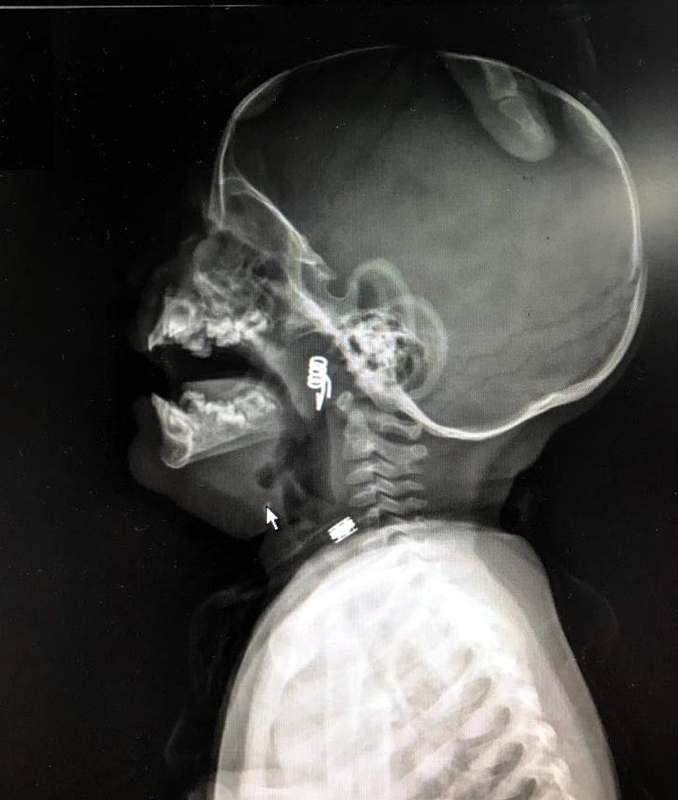

Nevşehir Devlet Hastanesi Acil Polikliniği'ne getirilen bebeği, Acil Nöbetçi doktoru Mustafa Alpaslan muayene ederek gerekli tetkikleri yaptı. Çekilen röntgen filmlerinde mandal yayının lokalizasyonu ve durumu belirlendi. Daha sonra, KBB Uzmanı Op. Dr. Ahmet Cevatzade tarafından yapılan başarılı ameliyat sonucunda bebeğin genzine saplanan mandal yayı çıkartıldı.